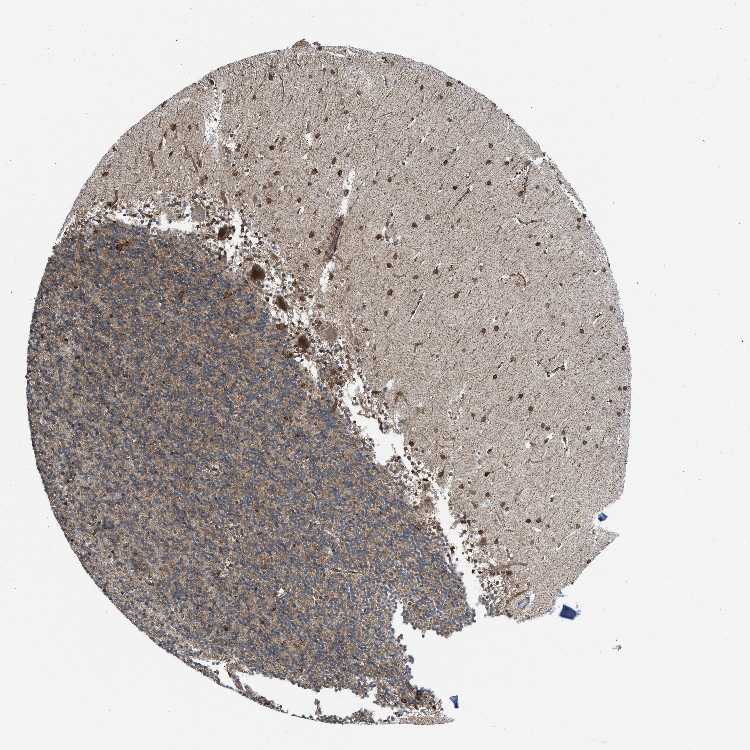

BRAIN CEREBELLUM Show tissue menu

CEREBELLUM - Expression summary

CEREBELLUM - Antibody stainingi

Antibody staining in the annotated cell types in the current human tissue is reported as not detected, low, medium, or high, based on conventional immunohistochemistry profiling in selected tissues. This score is based on the combination of the staining intensity and fraction of stained cells.

Each image is clickable and will lead to virtual microscopy that enables deeper exploration of all samples and also displays staining intensity scores, fraction scores and subcellular localization as well as patient and tissue information for each sample.

Antibody HPA002025Antibody CAB014894

Purkinje cells Not detectedHigh

Cells in granular layer HighHigh

Cells in molecular layer MediumHigh